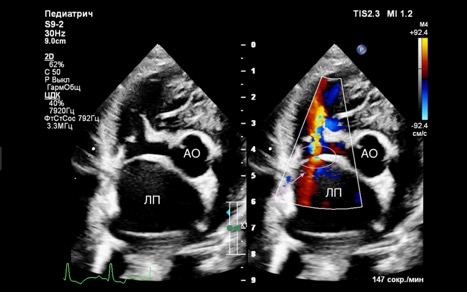

- В течение первых суток, а также на 14-й и 30-й дни после оперативного вмешательства на эхокардиографии выявлялось устойчивое наличие межпредсердного шунта со сбросом слева направо без признаков значимой объемной перегрузки правого желудочка (рис. 6).